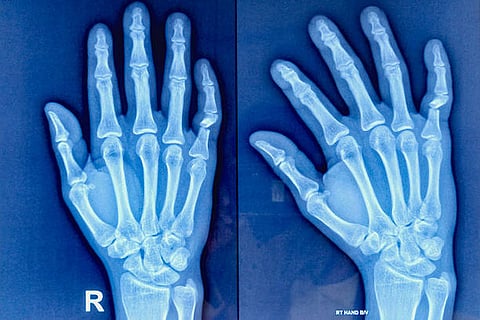

लेकिन लगभग 20 से 30 प्रतिशत लोगों में, जिनको सोरायसिस होता है, आगे चलकर जोड़ों में दर्द और सूजन भी शुरू हो जाती है। इस स्थिति को सोरायटिक आर्थराइटिस कहा जाता है। यदि इसका इलाज समय पर न हो, तो यह हड्डियों और जोड़ों को स्थायी नुकसान पहुंचा सकती है।

जिन लोगों में सोरायटिक आर्थराइटिस विकसित हो जाता है, उनमें फाइब्रोब्लास्ट कोशिकाओं की सुरक्षात्मक क्षमता कम हो जाती है। शोध के अनुसार, जब इन कोशिकाओं की सुरक्षा शक्ति घट जाती है, तो जोड़ों में पहुंची हुई प्रतिरक्षा कोशिकाएं अनियंत्रित हो जाती हैं। इसके बाद वे जोड़ों में सूजन पैदा करती हैं। यही सूजन आगे चलकर दर्द, अकड़न और हड्डियों को नुकसान पहुंचाती है।

अब तक अधिकतर मामलों में सोरायटिक आर्थराइटिस का पता तब चलता है जब जोड़ों में दर्द और सूजन शुरू हो चुकी होती है। उस समय तक कुछ नुकसान हो चुका होता है।